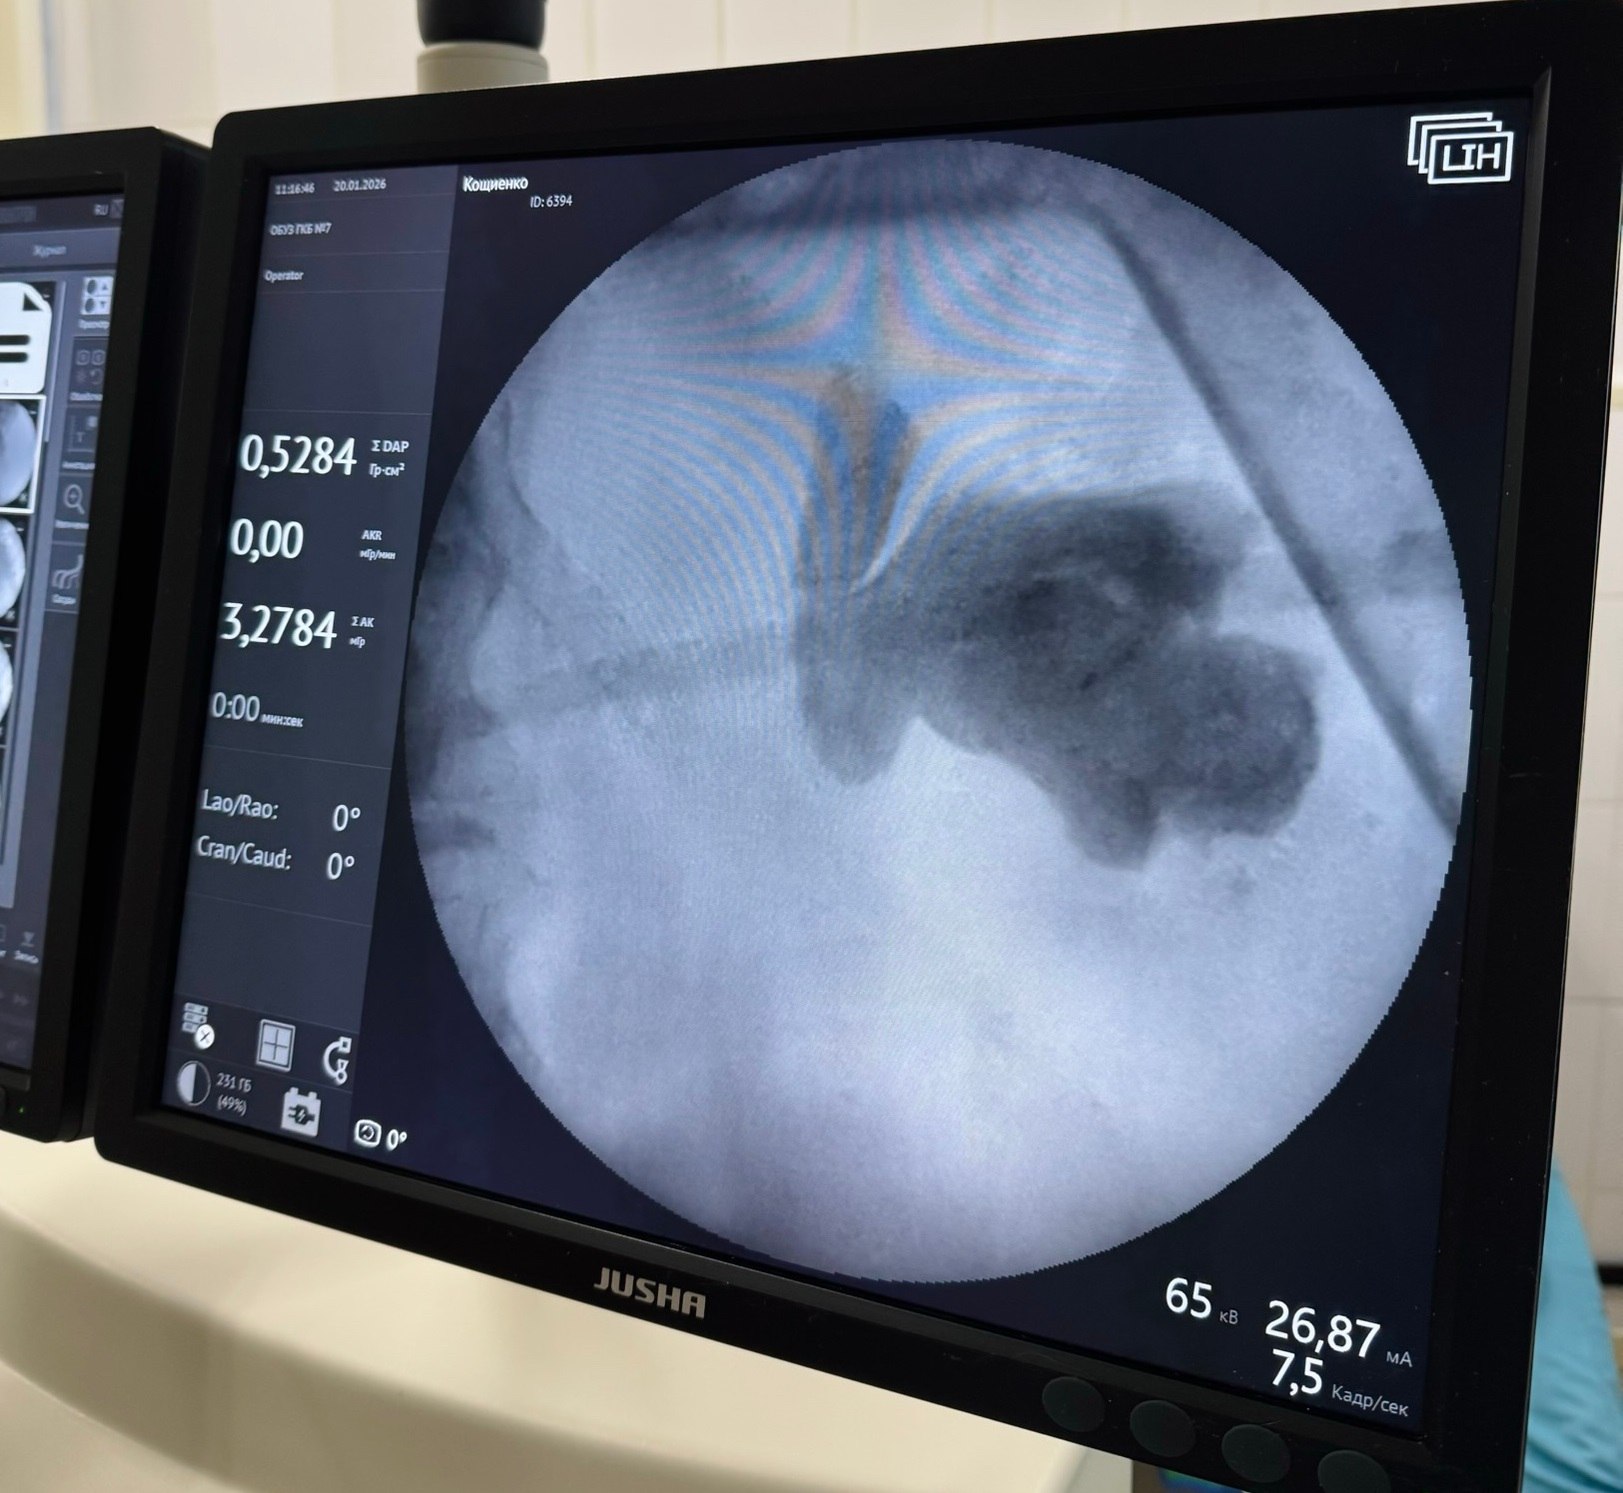

Совершили чудо и подарили надежду на здоровое будущее. Урологи 7-й Ивановской городской больницы удалили пациентке камень, который занимал почти всю площадь почки. Это максимальный размер образования, возможный для организма. Ситуация осложнялась еще и тем, что его мигрировавший фрагмент частично перекрывал мочевыводящие пути. Операцию провели врачи-урологи Дмитрий Болдин и Павел Соломатников. При помощи лазера они одномоментно раздробили камень и извлекли его через небольшой прокол в поясничной области.